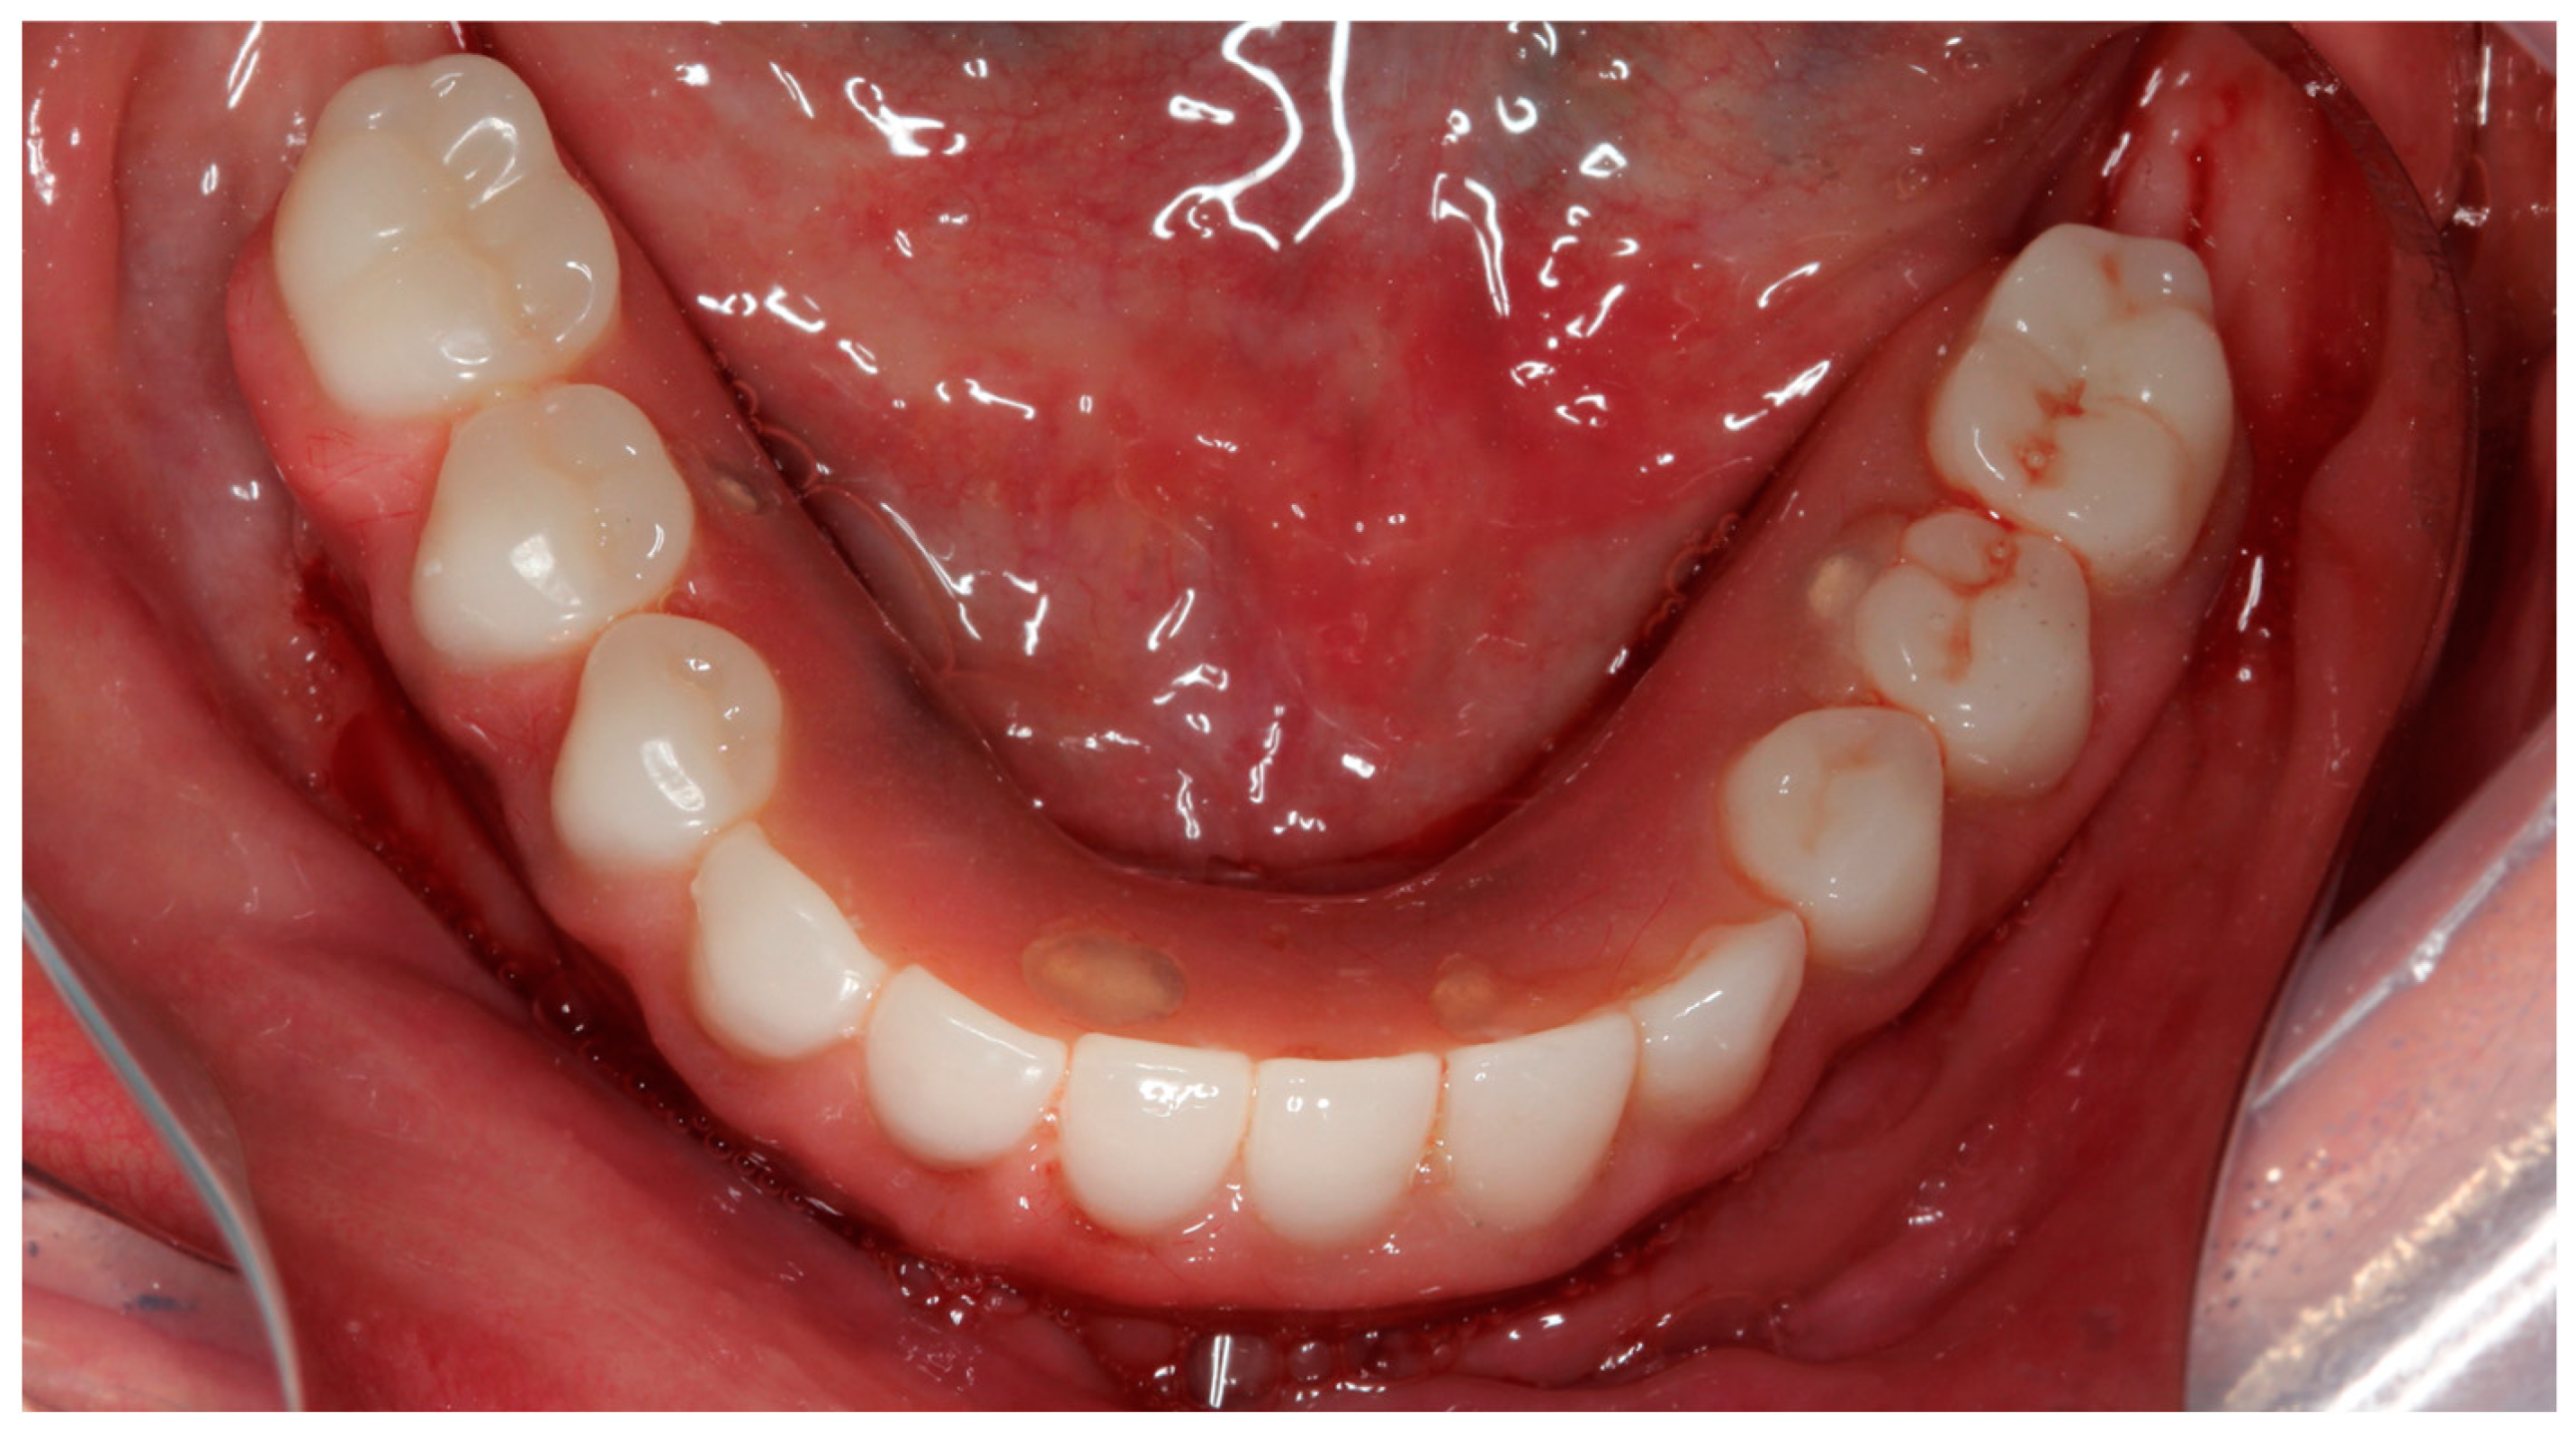

Implants with IT values equal to or higher than 75 Ncm were included in the study for follow-up and measurements, while implants with IT values lower than 75 Ncm were not marked as being of primary interest to this study. Despite this, when all four implants reached torques equal to or greater than 45 Ncm [22], immediate loading was performed. Straight multi-unit abutments were tightened to the anterior implants with a torque of 32 Ncm, and 17° or 30° angled multi-unit abutments (Dérig, São Paulo, Brazil) were drawn to the distal tilted implants with a torque of 20 Ncm [19]. After placing the abutments, the surgical wounds were sutured with 4-0 silk thread (Ethicon, São Paulo, SP, Brazil) (Figure 10).

Figure 10.

Occlusal view of the mandible after multi-unit covers were installed and sutured with 4.0 silk thread.